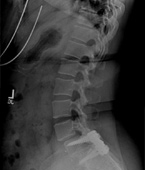

Before

After